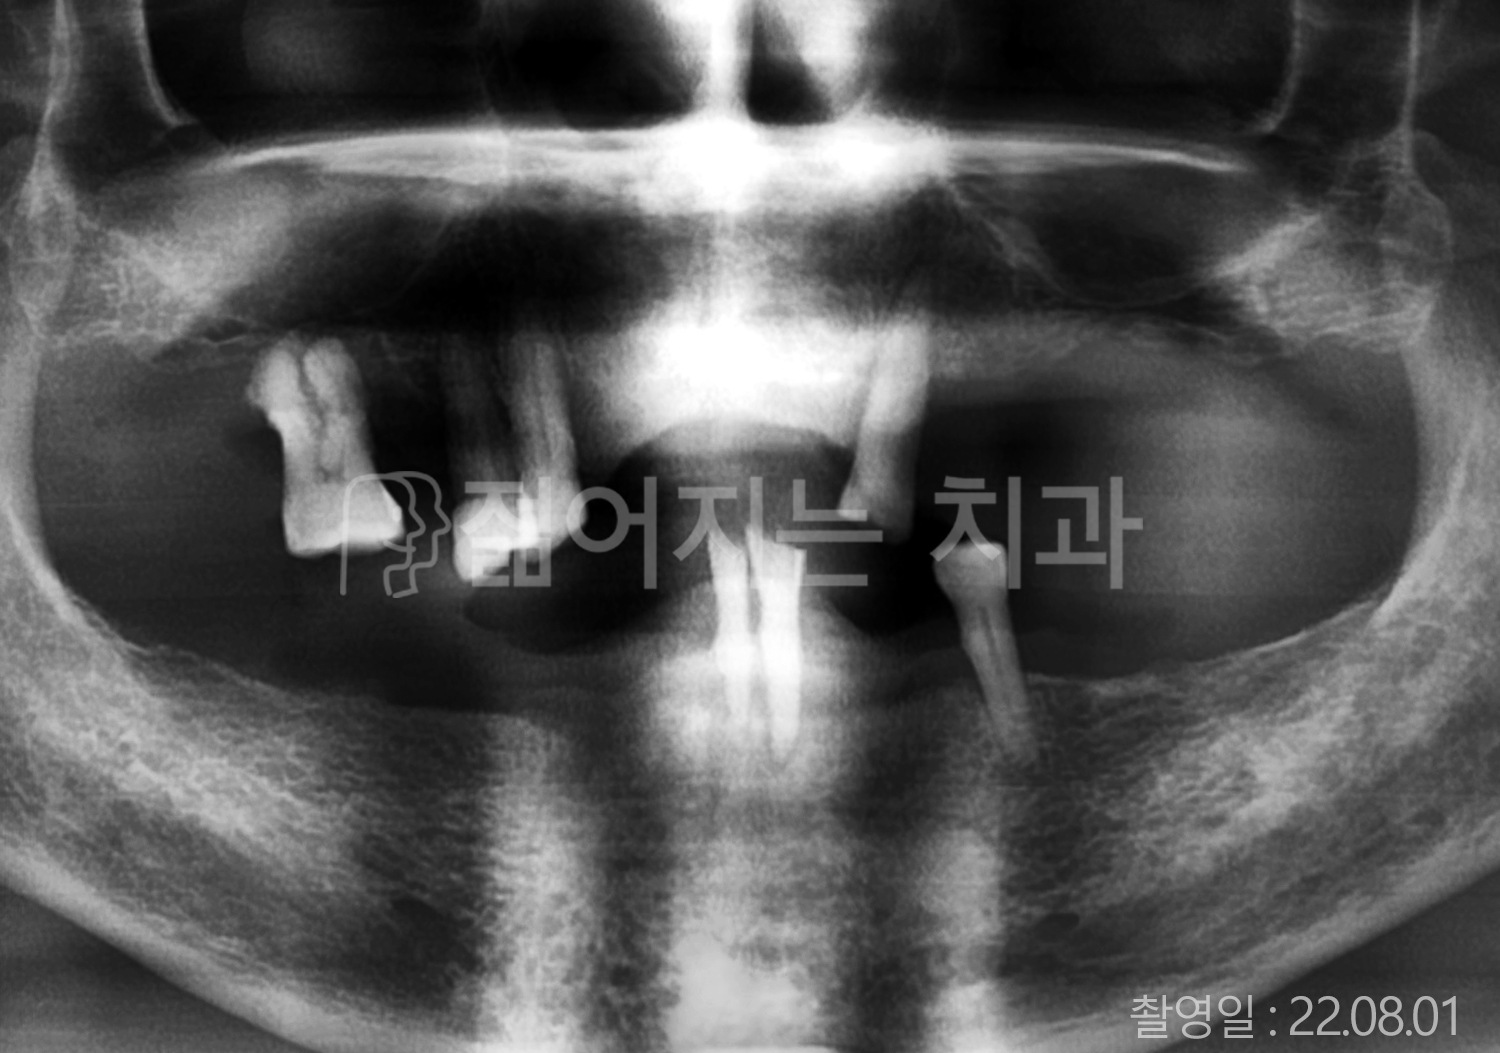

• 50대 고혈압, 당뇨, 고지혈증 전체치아 10개 이상 임플란트

• 60대 골다골증, 간경화 전체치아 10개 이상 임플란트

• 60대 고혈압, 고지혈증 전체치아 10개 이상 임플란트

• 50대 고혈압, 당뇨 전체치아 10개 이상 임플란트